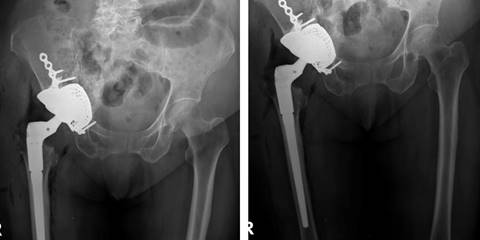

Se realiza abordaje quirúrgico sobre cicatriz previa tipo Hardinge,5 posterior a la profundización de planos se encuentra abundante tejido fibroso. Se realiza capsulotomía y se evidencia migración intrapélvica de componente acetabular y fractura de acetábulo de las dos columnas tipo transversa con defecto óseo acetabular central Paprosky IIIB. Se evidencia líquido intraarticular de aspecto inflamatorio y se descarta infección mediante la prueba de alfa-defensina (Synovasure® defensin) de Zimmer Biomet (Indiana, Estados Unidos). Se procede a la luxación controlada y remoción de componente acetabular y femoral. Se coloca aloinjerto cadavérico de cabeza femoral en fondo acetabular, cubriendo defecto central de tamaño aproximado de 4 × 5 centímetros (Figura 4A); después se coloca la malla metálica previamente moldeada de Zimmer Biomet (Indiana, Estados Unidos) en fondo acetabular (Figura 4B).

Figura 4: A) Colocación de aloinjerto óseo en fondo acetabular. B) Colocación de malla metálica en fondo acetabular sobre aloinjerto óseo.

Posteriormente, se realiza osteosíntesis de fractura acetabular con placa de reconstrucción de 3.5 milímetros 10 orificios más placa de tercio de caña 4 orificios con tornillos corticales respectivos de DePuy Orthopaedics (Indiana, Estados Unidos). Una vez estabilizado el acetábulo, se coloca cuña de tántalo de 50 × 10 milímetros más dos tornillos de fijación (40 y 35 mm) de Zimmer Biomet en defecto superior acetabular (Figura 5).

Figura 5: Colocación de cuña de tántalo superior de 50 X 10 milímetros.